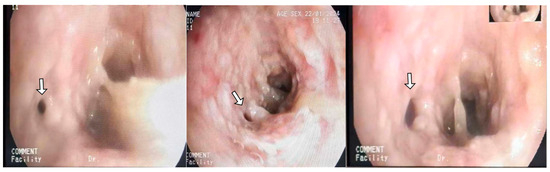

We report a bronchoscopic image of a 36-year-old with significant airway obstruction from obstructive tracheobronchitis secondary to invasive pulmonary aspergillosis. It is rare to see such a severe form of obstructive tracheobronchitis, likely caused by the patient’sp immunocompromised status and rapid progression nature [...] Read more.

We report a bronchoscopic image of a 36-year-old with significant airway obstruction from obstructive tracheobronchitis secondary to invasive pulmonary aspergillosis. It is rare to see such a severe form of obstructive tracheobronchitis, likely caused by the patient’sp immunocompromised status and rapid progression nature of influenza-associated pulmonary aspergillosis. Full article

Figure 1